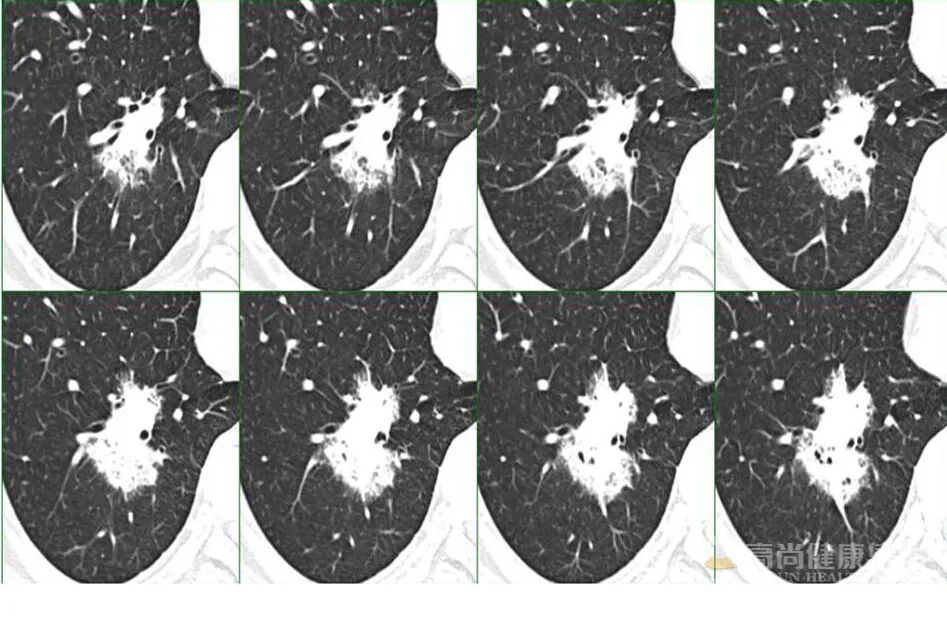

1、单一肺内病灶最主要是判断病变的性质,虽然比较像肿瘤,但仔细看病变内除了有支气管充气影,还有气泡影,病变局部边缘也有点模糊,因此这个炎症(脓肿)是有可能的,这个人肺泡灌洗出现克雷伯杆菌,结合病史那克雷伯肺炎(脓肿)是有可能的。

4、PPL 肿块型是有可能,内支气管扩张伴僵硬?

7、MALT 有可能,代谢上比较符合,病灶境界较清楚,周围还算干净,渗出不明显,支气管局部狭窄,患者无明显症状,就是 PPD 试验强阳不知怎么解释,不会是两者合并存在吧。

9、孤零零一个病灶,主要围绕气管生长,所示支气管基本通畅。有钙化,病灶整体密度偏高,病灶周围有少许磨玻璃,总体感觉偏向感染性病变,或者在已有病变 (如淀粉样变性什么的 (的基础上发生的感染,具体什么感染,结合临床,不象常见的,真菌放线菌等少见的要考虑下。

10、支气管迂曲扩张,考虑肺腺癌。

12、没有临床症状,单看影像,不看实验室检查结果的话,是比较像肺 MALT 的。

MALT 的支气管扩张并无支气管管壁的破坏。由于淋巴瘤组织浸润导致肺泡塌陷,支气管周围实质破坏造成的,这类支气管扩张在肿瘤治疗后有时可消失。

结节、肿块,边缘模糊

充气支气管粗大、扭曲

▼伴有空气支气管征充气的支气管粗大、扭曲;